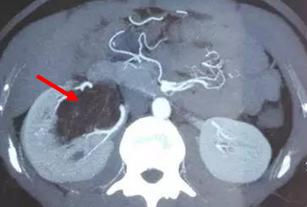

诊断通常依赖B超和CT或MRI:B超下表现为高回声结节,当然偶尔会有混合回声。CT通常显示肿瘤内部有极低密度值的脂肪成分。部分乏脂性错构瘤诊断较为困难,需依靠病例确诊。

CT上的表现为低密度灶,脂肪成分越多,密度越低;但是有些因为平滑肌成分为主,需要和肾癌相鉴别